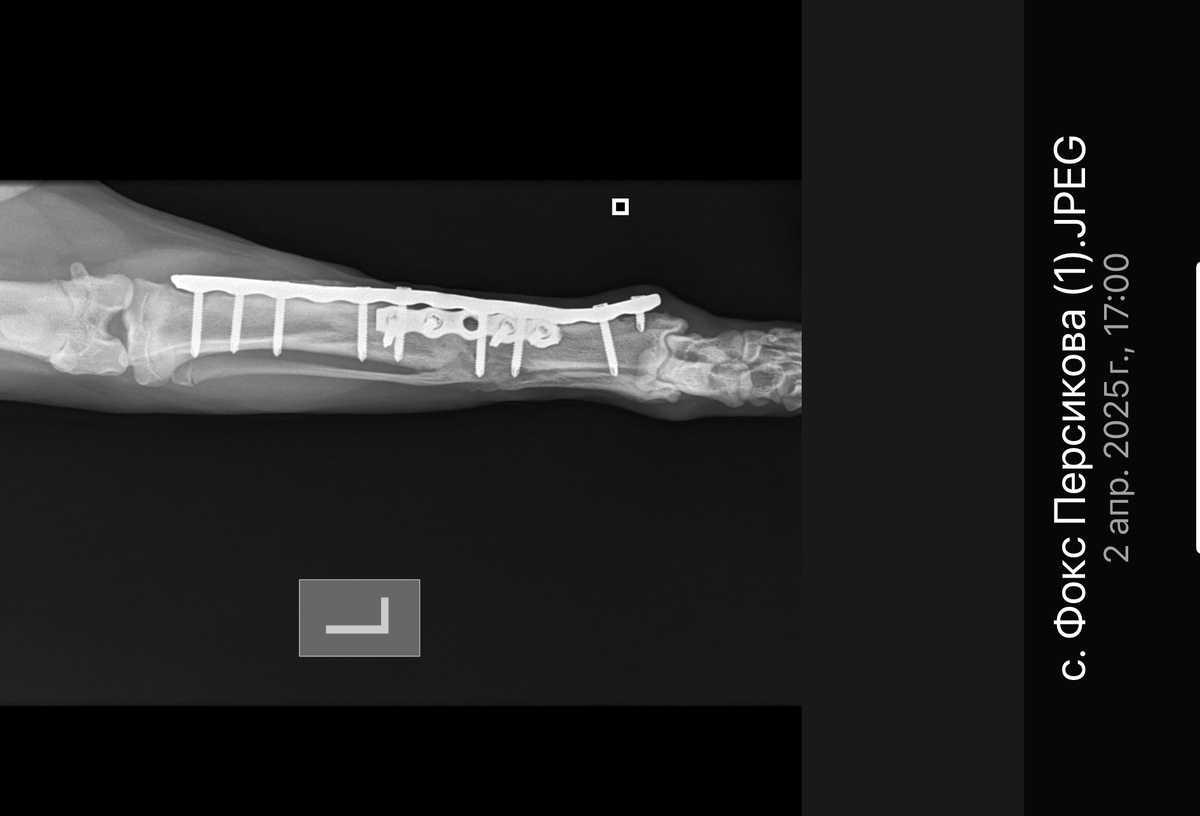

Перелом сросся, но оставят одну пластину для подстраховки и три винта

Обзорная рентгенография костей голени левой тазовой конечности в медио-латеральной и каудо-краниальной проекциях. Металоимпланты интактны. Консолидации линии перелома по гипертрофическому типу. Признаки инфекции кости в стадии разрешения.

Рекомендовано проведение частичного снятия металлоимплантов и взятие материала (кости) на бактериологический посев.